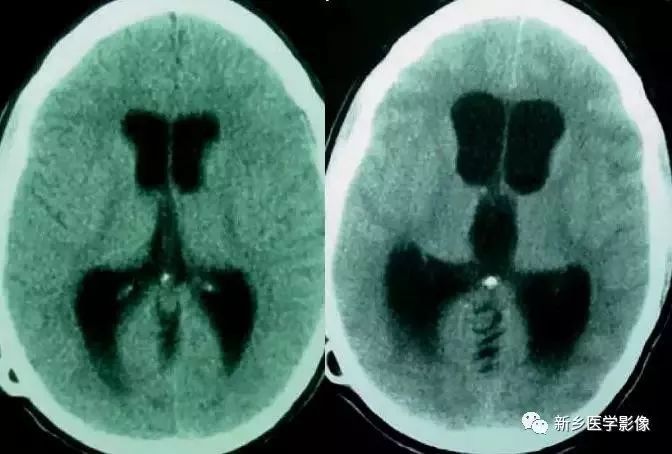

❹ Dandy-Walker’s综合症

又称第四脑室中侧孔先天性闭锁。在胚胎早期期,第四脑室正中孔及侧孔闭寒,导致四脑室呈囊性扩张,并伴有小脑蚓部及半球发育不良,扩张之四脑室向后发展,并与枕大池相连,使后颅窝扩大,小脑幕抬高。本病出现脑积水通常见于婴儿期,或者出生后即存在,但到成人期才发病。